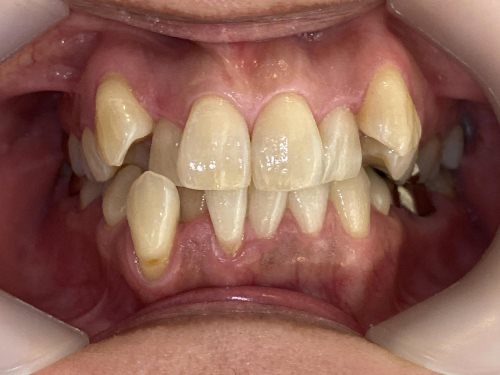

50代女性「前歯がガタガタで笑えない」マウスピース型矯正装置「インビザラインフル」で、非抜歯にて歯並びと噛み合わせを治療し、見た目を改善した症例

「前歯のガタガタがひどく、人前で笑えない。歯を抜かずに治したい」とご相談いただきました。

拝見すると、上下左右の前歯12本(中切歯/1番・側切歯/2番・犬歯/3番)が、デコボコに生えている状態の「叢生(そうせい)」でした。